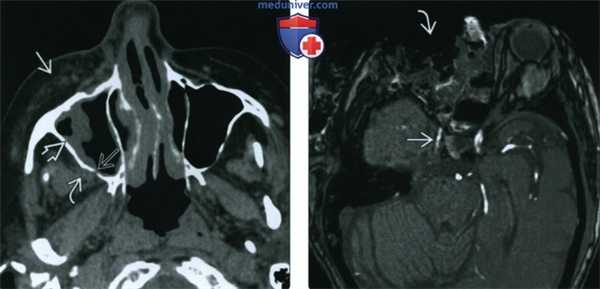

Пациент с жалобами на боли в области правой верхней челюсти, возникший после пересадки костного мозга в связи с острым миелоидным лейкозом. При КТ наблюдается инвазивный синусит, вызванный грибами рода Aspergillus с инфильтрацией мягких тканей лица и подвисочной ямки, преимущественно с правой стороны (а). Хроническая форма (b), наблюдается увеличение плотности в центре очага.